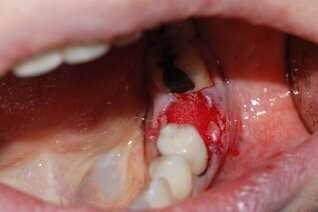

Dopo l’anestesia locale, è stato scollato un lembo a spessore totale e il dente estratto in modo atraumatico (Fig. 1). Successivamente, l’alveolo post-estrattivo è stato zeppato con granuli di osso bovino decellularizzato (Re-Bone®, Ubgen, Padova/Italy) e utilizzata una membrana di pericardio bovino come barriera (Shelter® Membrane, Ubgen, Padova/Italy) (Fig. 2).